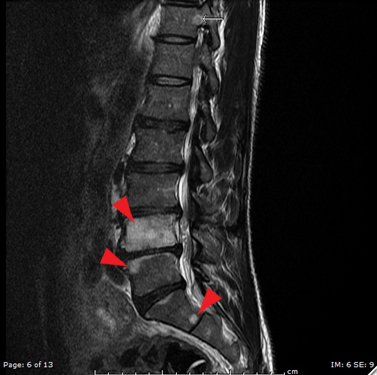

DOI: https://doi.org/10.21980/J8563BThe MRI showed extensive spondylotic changes suggestive of malignancy (red arrows) with severe spinal canal stenosis at the lumbar spine L3-L4 (purple arrows) level contributing to clumping of cauda equina nerve roots and severe bilateral neuroforaminal narrowing with diffuse disc bulges abutting the exiting nerve roots at multiple levels. Findings also showed a hypo-attenuated tumor (blue arrow) and hyper-attenuated loculated tumor (green arrow) consistent with renal cell carcinoma (RCC).